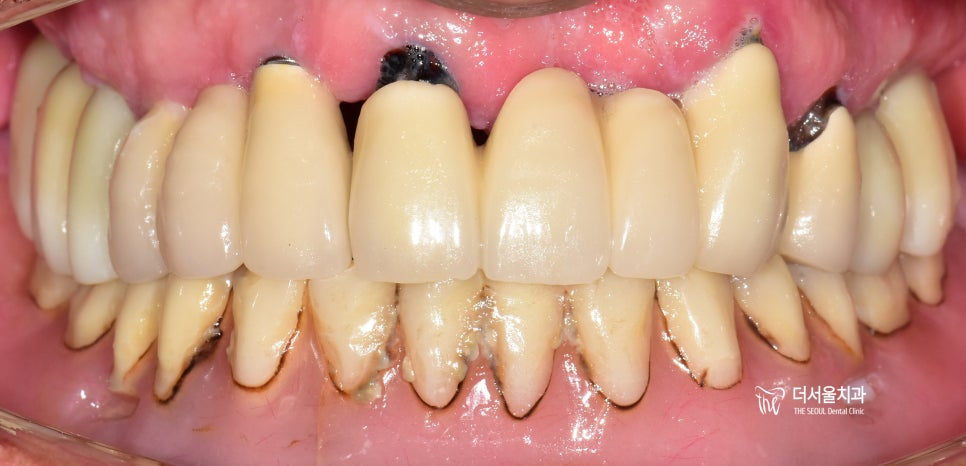

앞니 는 기능적인 측면뿐만 아니라 심미적인 요소도 함께 고려해야 됩니다. 그래서 보철의 형태와 색상 등을 여러 번 체크하고 확인하는